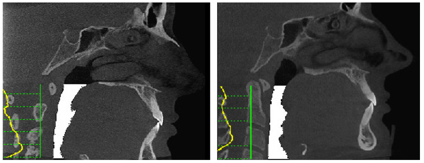

State of the art 3D technology for diagnosis of patients before and after developmental procedures.